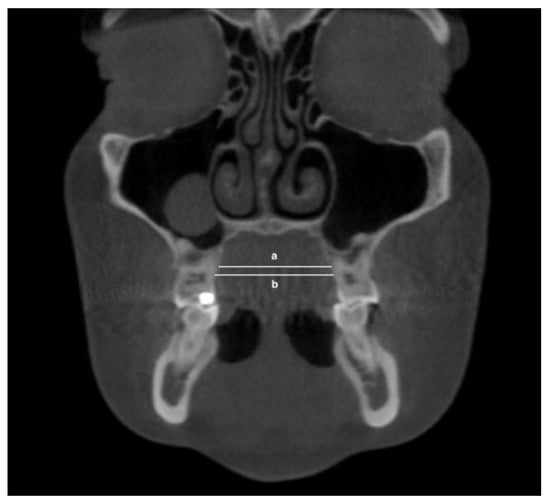

- Maxillary inter-buccal bone widths: from the right to the left points at the level of hard palate, alveolar crest and furcation (Figure 1)